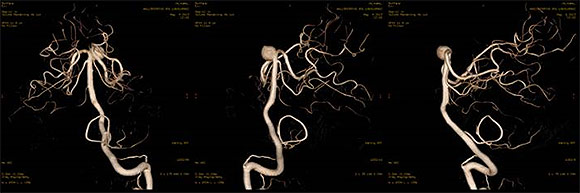

当院導入装置では血管の3D撮影や、CT類似の画像の取得も可能です。

![]() |

| アンギオによる脳血管3D撮影 |